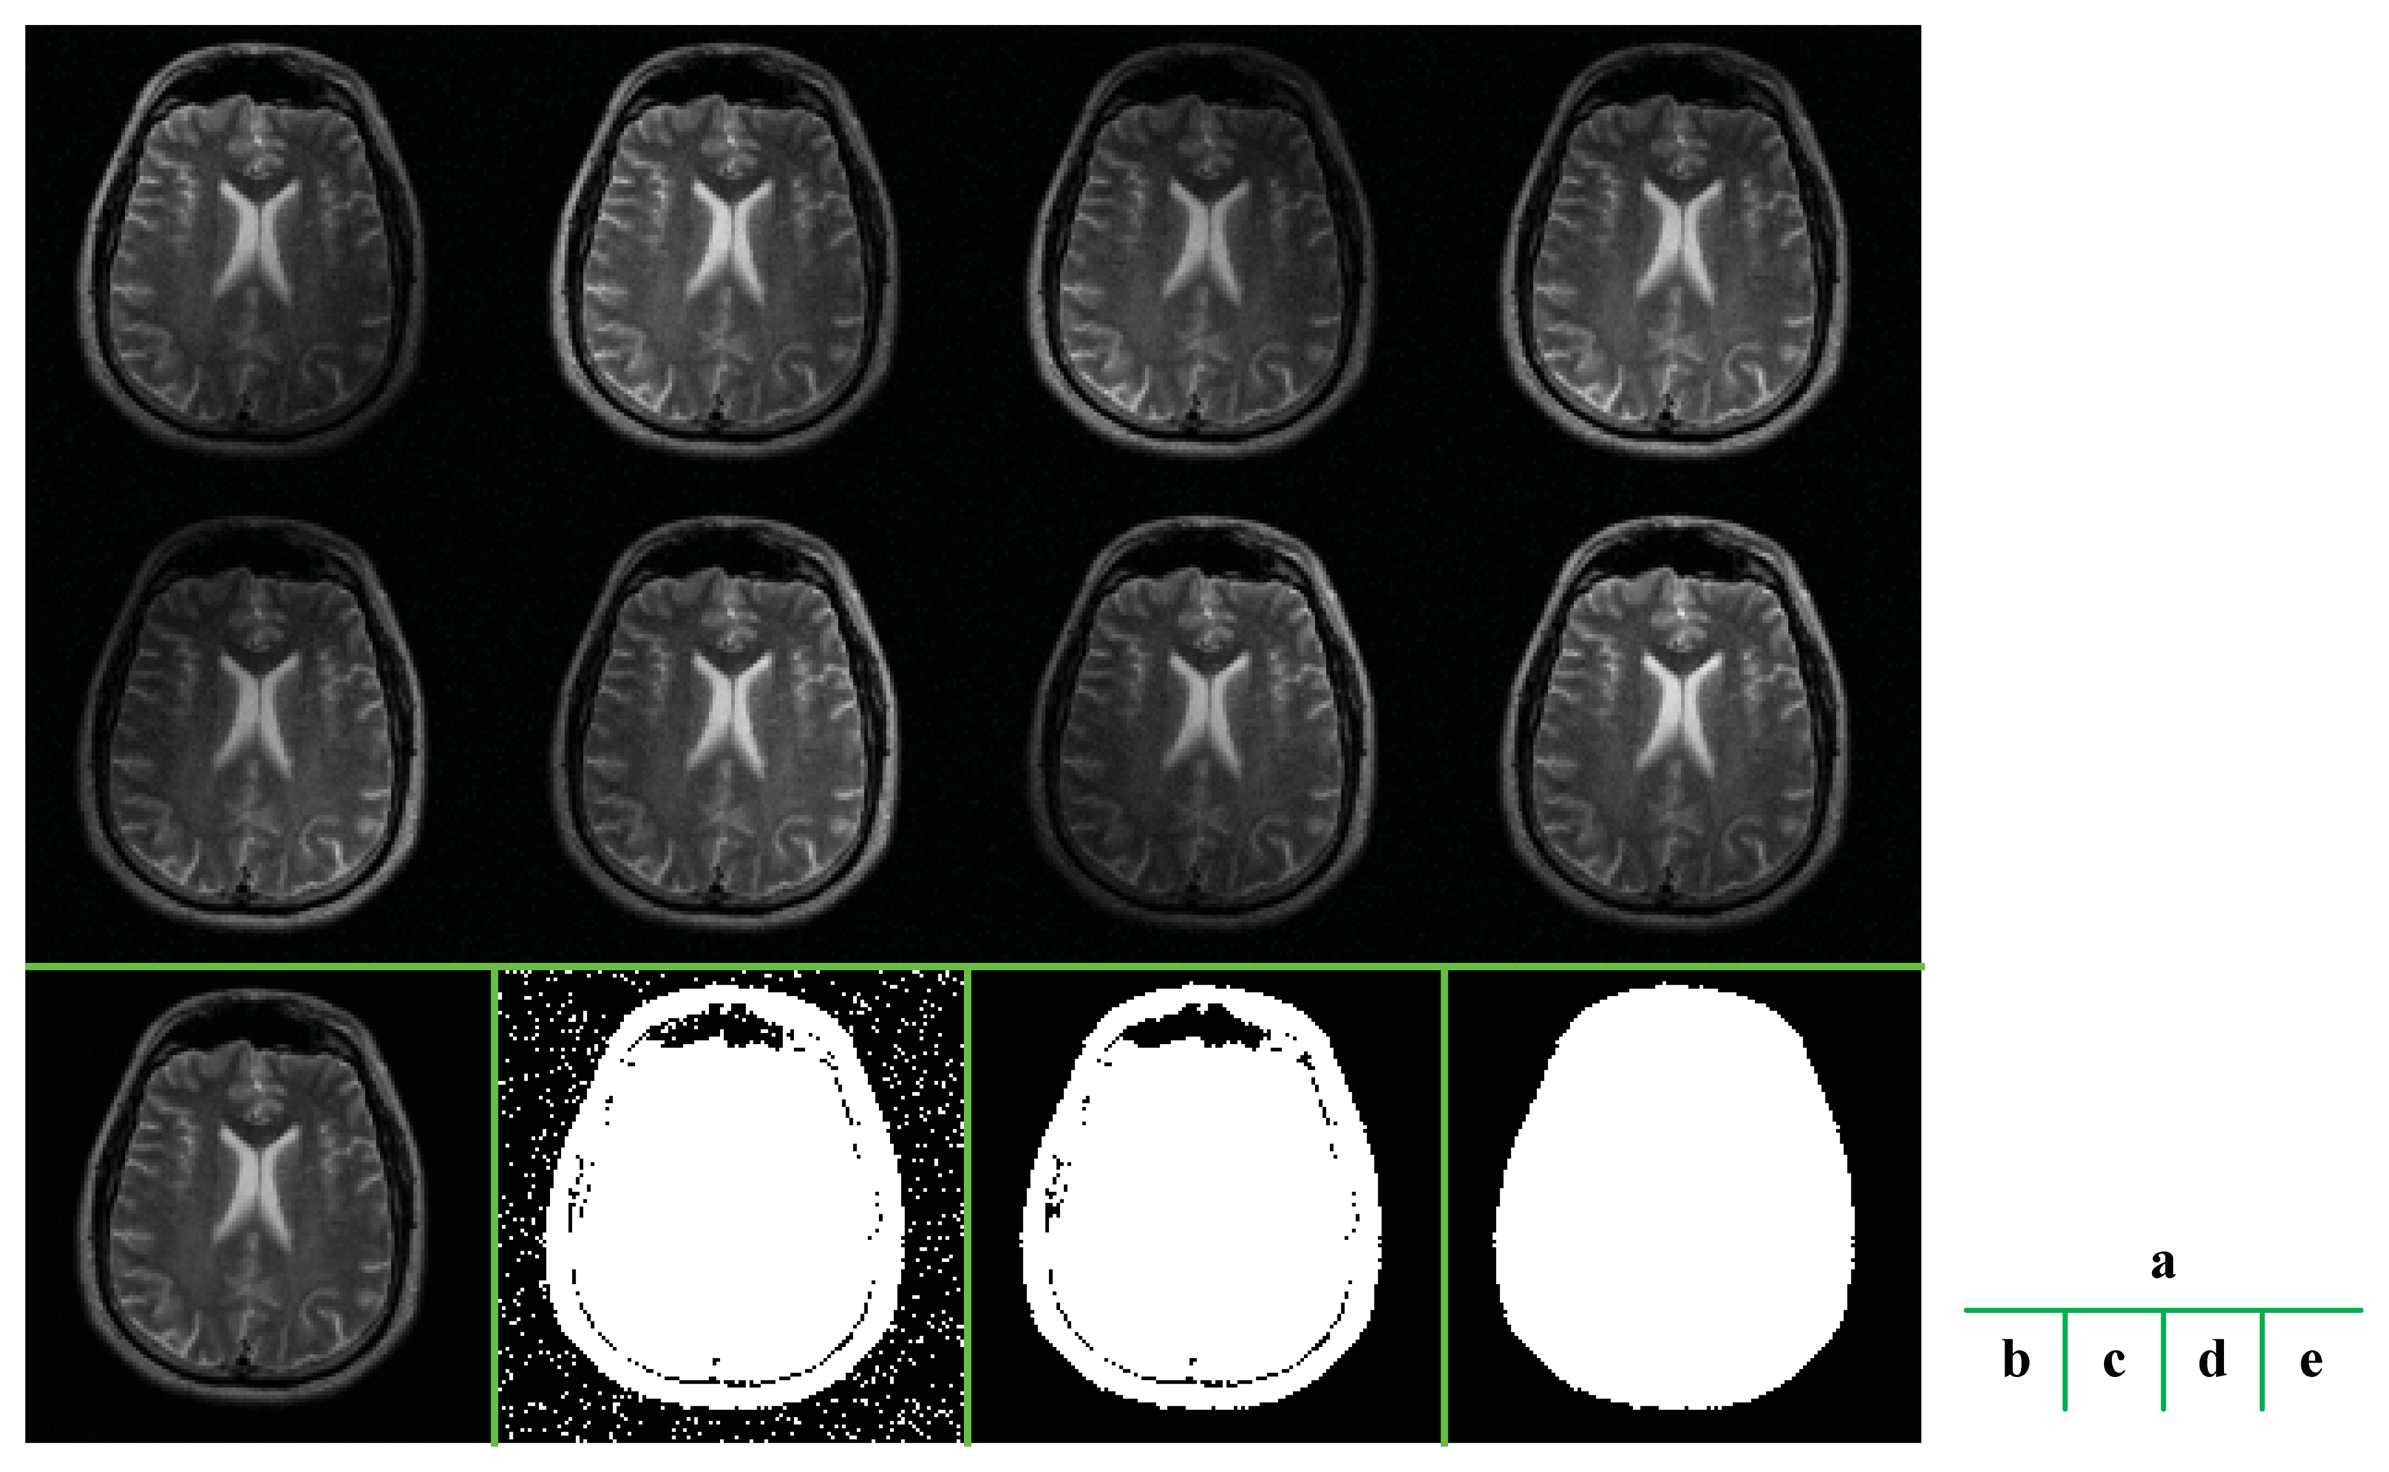

The ROS is detected from the scout images of eight channels [14] (Figure 3). Let Oi denotes the scout image of the ith channel, the ROS is calculated from following procedures.

The mean essence of the algorithm is thresholding based on the signal-to-noise ratio (SNR), because the brain area usually contains higher signal than the background does. But other morphological operations are also necessary to ensure an example of these procedures is illustrated in Figure 3. The final extracted ROS was very close to the shape of the brain.